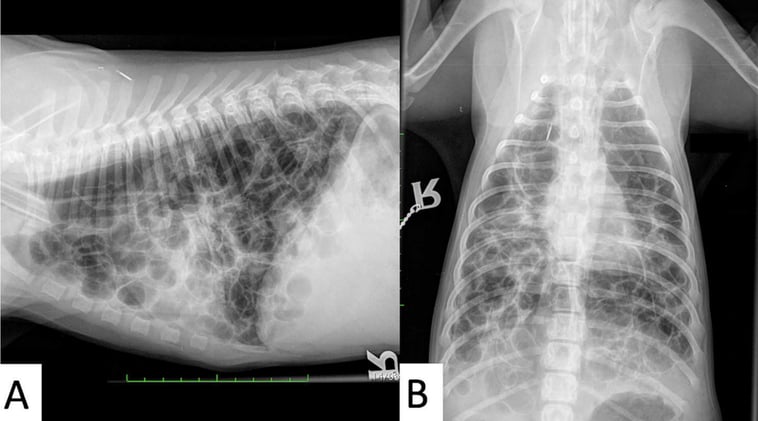

Feline